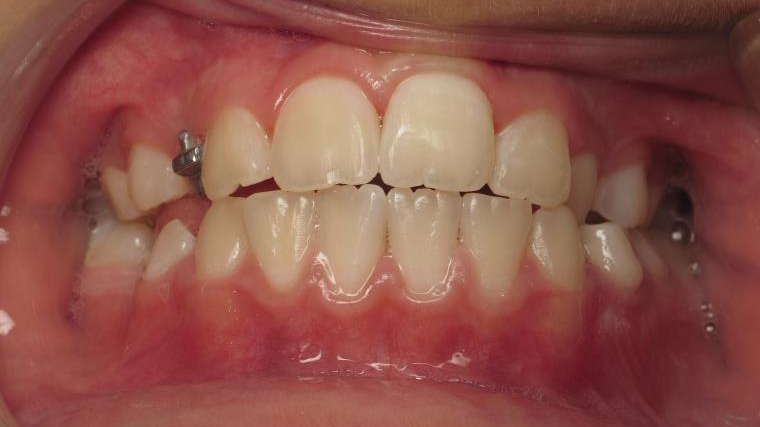

appareillage multibagues pendant 3 ans

bilan début et fin de traitement